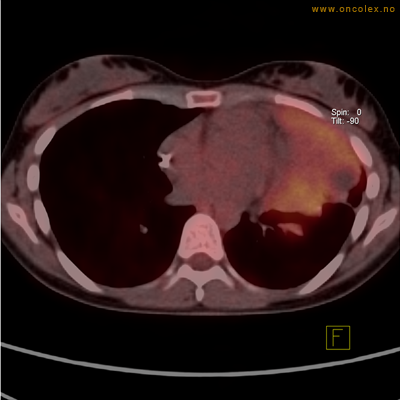

Vev som tar opp mer radioaktivt stoff, synes som hvite områder som lyser opp mer i forhold til annet vev som tar opp mindre sukker.

Moderat opptak i bløtvevssarkom venstre halvdel av brystkassen. Områder med lavere opptak antas å skyldes dels betennelse som skyldes svulsten, dels svulstnekrose.

Moderat opptak av FDG i bløtvevssarkom venstre halvdel av brystkassen. Områder med lavere opptak antas å skyldes dels betennelse som skyldes svulst, dels svulstnekrose.